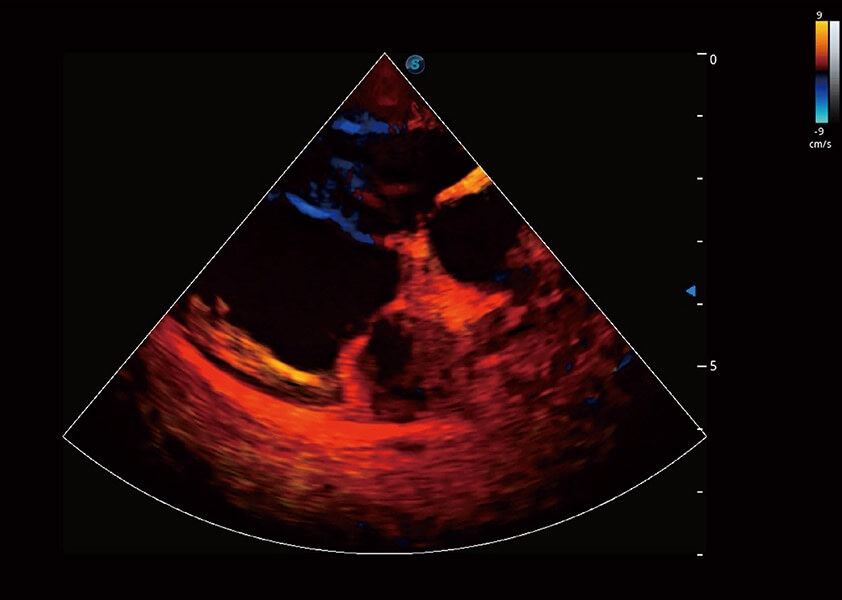

• TDI 組織多普勒成像

實(shí)時(shí)用顏色表示心肌組織運(yùn)動(dòng),觀察和定量組織的運(yùn)動(dòng)情況,對(duì)快速檢測(cè)與評(píng)估心肌的灌注和活性、電傳導(dǎo)及心肌收縮和舒張功能等均能提供重要的診斷信息。

(犬)四腔心血流

(犬)心臟組織多普勒